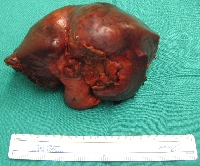

Πρόκειται για άνδρα ασθενή 44 ετών, ο οποίος υποβλήθηκε σε αξονική τομογραφία άνω κοιλίας στα πλαίσια διερεύνησης επιγαστραλγίας. Βρέθηκε μάζα στο 4ο, 5ο και 8ο ηπατικό τμήμα (εικόνα 1). Δε διαπιστώθηκαν σημεία κίρρωσης. Η διερεύνηση για πιθανή πρωτοπαθή εστία εκτός ήπατος ήταν αρνητική. Τέθηκε η διάγνωση της πρωτοπαθούς ηπατικής μάζας (HCC vs CCa). Η εικονική αριστερή εκτεταμμένη ηπατεκτομή με ανάλυση MEVIS (εικόνα 2) οδήγησε σε ηπατικό κολόβωμα μεγέθους 30% του αρχικού, ποσοστό που κρίθηκε ανεπαρκές. Η εικονική κεντρική ηπατεκτομή με ανάλυση MEVIS (εικόνα 3) οδήγησε σε ηπατικό κολόβωμα μεγέθους 65% του αρχικού, ποσοστό που κρίθηκε ικανοποιητικό. Για το λόγο αυτό, ο ασθενής υποβλήθηκε σε κεντρική (parenchymal sparing) ηπατεκτομή (εικόνα 4). Tο παρασκεύασμα αποτελούνταν από τα ηπατικά τμήματα 4b, 5, 8- και τη χοληδόχο κύστη (εικόνα 5). Η διατομή του (εικόνα 6) ανέδειξε μάζα μεγέθους 9 εκατοστών με κάψα, η οποία αφαιρέθηκε άθικτη. Τα ιστολογικά χαρακτηριστικά του όγκου (CK7+, CK19+, CK20-) ήταν συμβατά με CCa (mass forming). Ο ασθενής έλαβε εξιτήριο τη 10η μετεγχειρητική ημέρα.